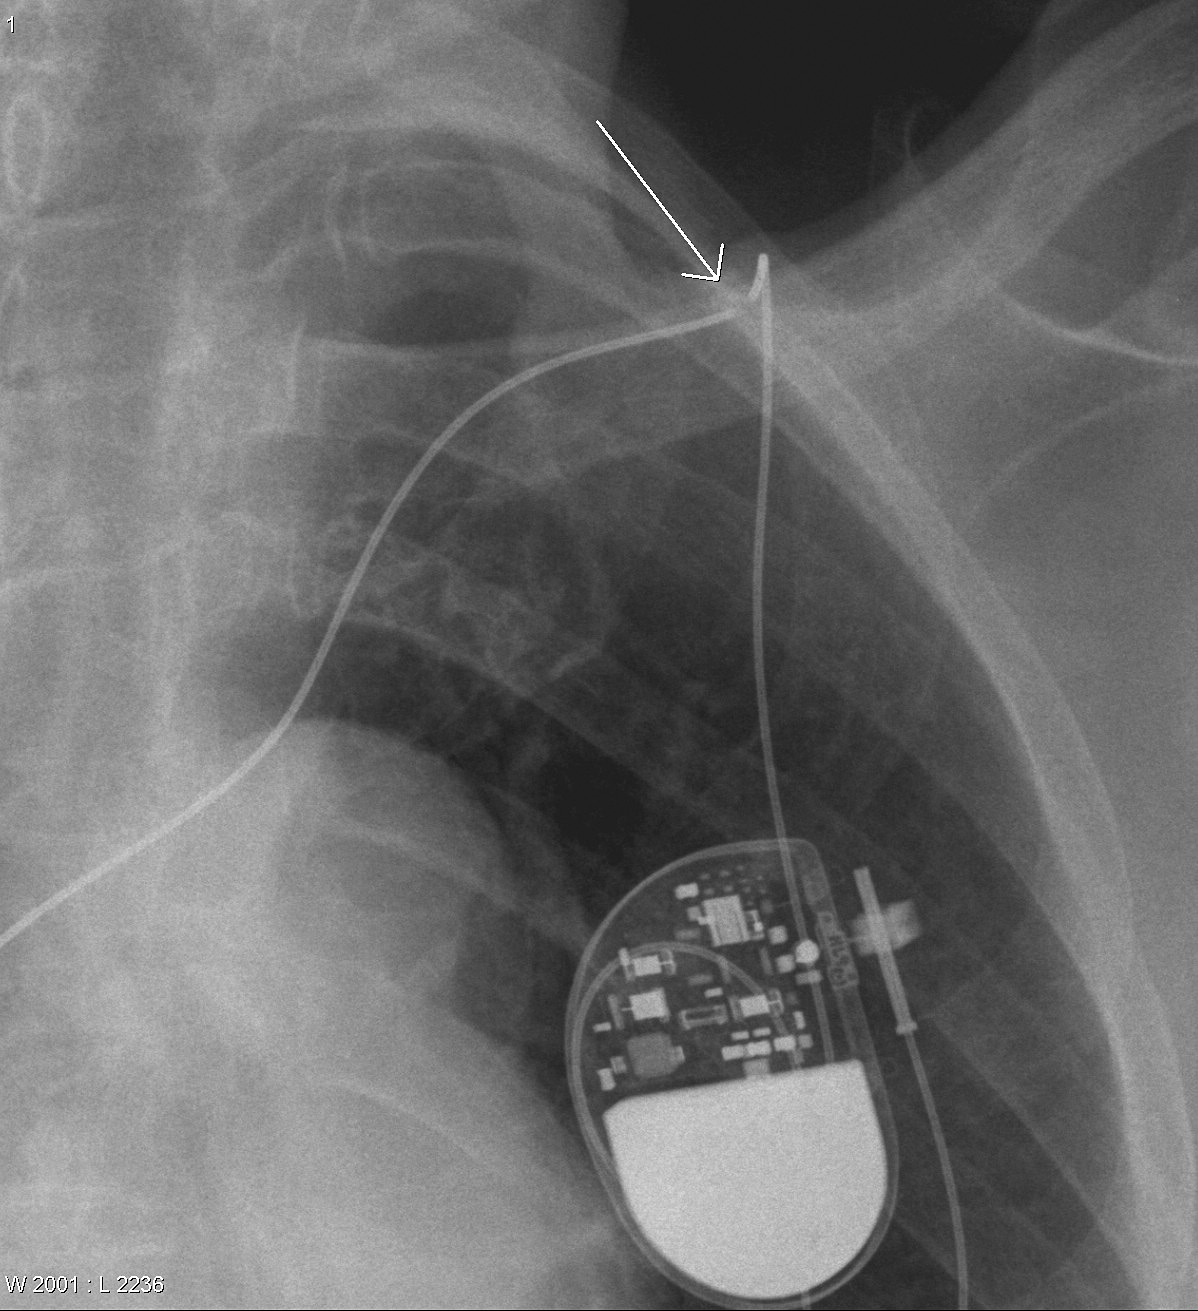

Gallery Cardiac Other Broken PM wire

Broken PM wire